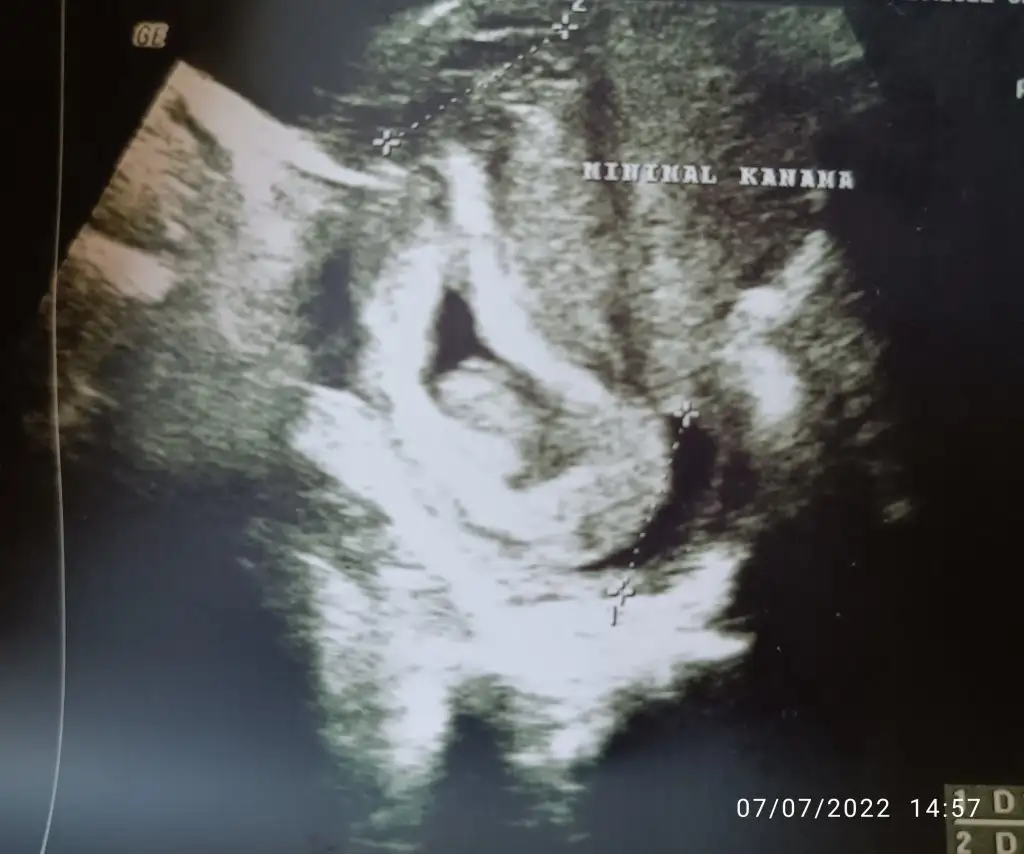

İyi haberler, kalp atışı iyi, buyuklugu tam haftasiyla uyumluymus.10 hafta 3.12 cm.5 gündür aktif kanamanın olmamasi iyi dedi.

Kötü haber kanama alanlarım artmis .ustte vardı altta da olusmus . İlk resimde siyah alan da görünen kanama alani beni biraz korkuttu dedi doktor. Plasentaya zarar verebilir plasenta ayrilirsa siddetli kanaman olur zaten dedi.doktora 12. Haftaya gelip rahatlasam artik dedi. Hayir yolumuz uzun 20. Haftalara kadar rahim sekli bozuklugundan kaynaklanan risk devam edecek dedi.